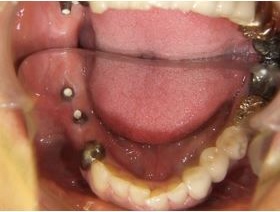

50歳代 男性 右下臼歯部 インプラント植立

インプラントを埋め込んだところ(上から)